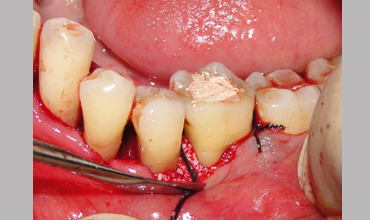

NON SURGICAL MANAGEMENT OF ENDODONTIC LESION AND SURGICAL MANAGEMENT OF PERIODONTIC LESION